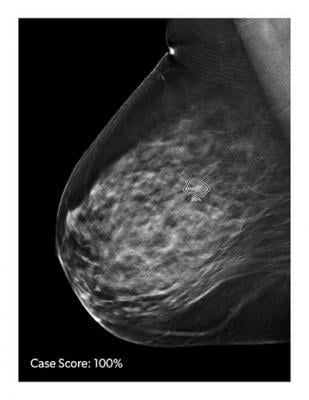

October 28, 2019 — Artificial intelligence (AI) helps improve the efficiency and accuracy of an advanced imaging ...

Despite decades of progress in breast imaging, one challenge continues to test even the most skilled radiologists ...

Screening digital breast tomosynthesis (DBT) results in “significantly increased CDR [cancer detection rates]” compared to full-field digital mammography (FFDM), according to an ahead-of-print article in the March issue of the American Journal of Roentgenology (AJR). DBT offered improved results irrespective of tumor type, size or grade of cancer.